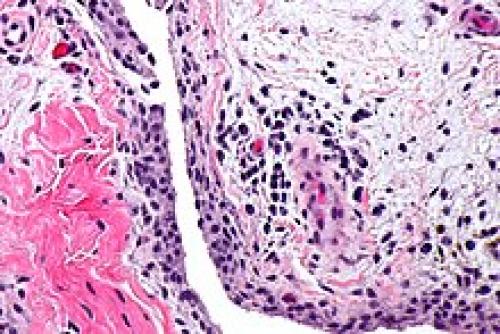

Синови́т , лат. synovitis (от лат. (membrana) synovialis — синовиальная оболочка и суффикса -itis , обозначающего воспалительный процесс ) — воспаление синовиальной оболочки , ограниченное её пределами и характеризующееся скоплением выпота в выстилаемой ею полости (в синовиальной сумке , влагалище сухожилий,).

- Острый синовит – сопровождается утолщением, полнокровием и отеком синовиальной оболочки. Выпот представляет собой полупрозрачную жидкость, иногда – с видимыми невооруженным глазом хлопьями фибрина.

- Хронический синовит – проявляется развитием фиброзных изменений в капсуле сустава. В ряде случаев ворсинки синовиальной оболочки разрастаются, на оболочке возникают фибринозные наложения, свисающие с полость сустава (ворсинчатый синовит). При отделении наложения трансформируются в так называемые «рисовые тельца», которые свободно перемещаются в суставной жидкости и дополнительно травмируют синовиальную оболочку.

Акварельный рисунок острого синовита коленного сустава, показывающий начало распада хряща внутреннего мыщелка.